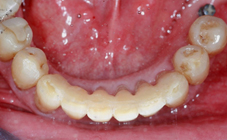

Arcade mandibulaire avant traitement orthodontique, séquelles de maladie parodontale

Après traitement orthodontique et réalisation d’une attelle fibrée (courtoisie Dr Patrick Fournier)